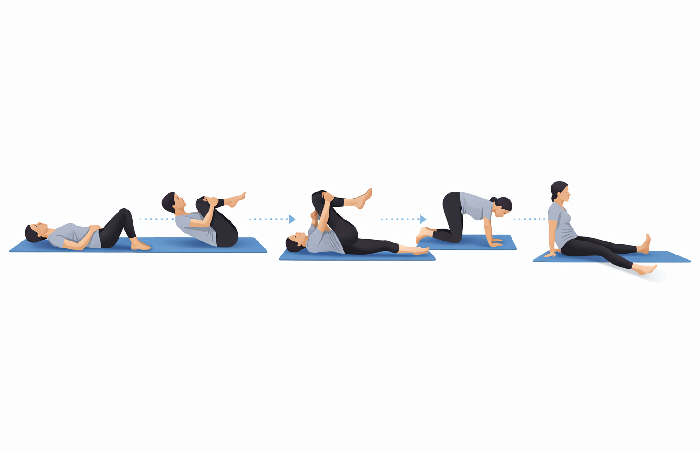

Step 2 — Knee-to-Chest Stretch (2 minutes)

- From the same position, slowly draw one knee toward your chest.

- Hold your shin (not your knee joint) gently.

- Hold for 20–30 seconds. Feel a gentle release in the lower back and glute.

- Lower slowly. Repeat on the other side.

- Complete 3 repetitions per side.

Why: This position provides a mild decompression of the lower lumbar area and a streatching of the piriformis and gluts two of the more common compression sites for sciatica.

Centralization check: Does the pain move toward your back? Good. Does it move down your leg? Stop this stretch.